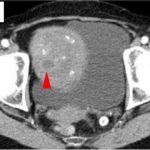

An important component of the microscopic machinery that drives cell death has been identified by Walter and Eliza Hall Institute scientists.

Studying the 'pro-death'...